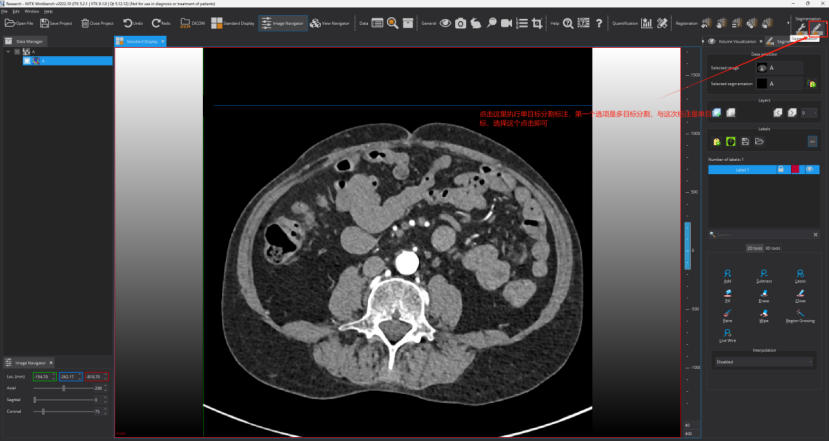

Step 6: 执行标注。按照图片的指示进行操作

点击之后可以进行标注了,这个地方可选择的标注工具比较多,下图框出部分即为标注相关工具,标注者需要进行摸索尝试一下!需要用什么标注工具,选择一下即可,然后在图上进行标注及修改